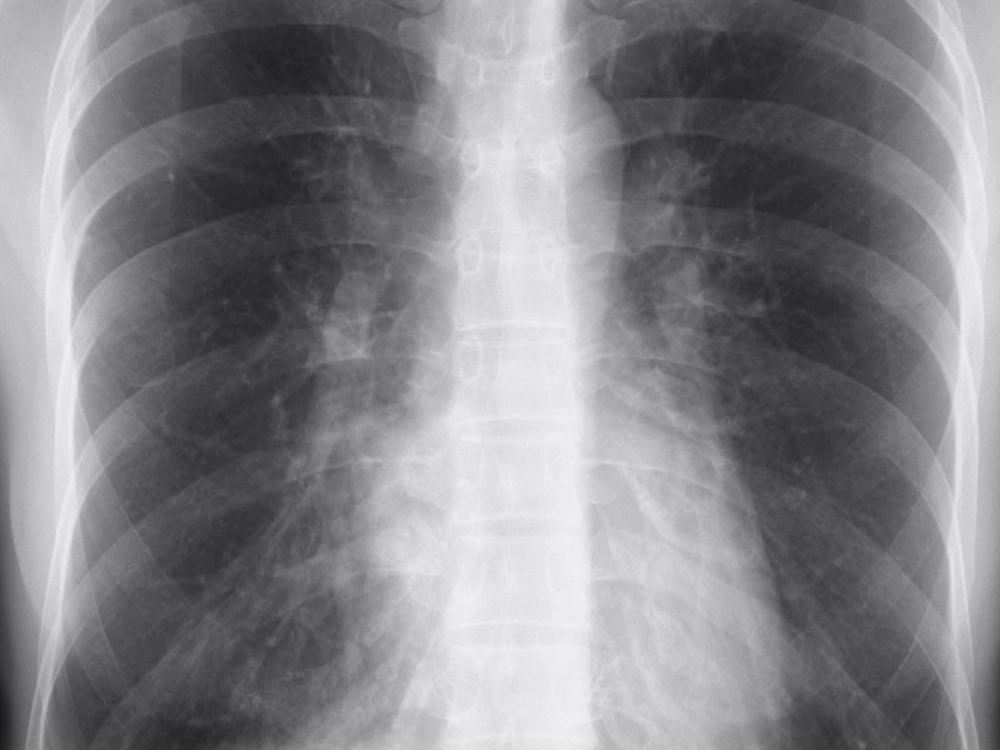

갈비뼈의 미세 손상은 단순 엑스레이(X-ray)로 잘 보이지 않는 경우가 많습니다. 이 경우 CT(컴퓨터 단층촬영) 또는 초음파 검사가 보조적으로 사용될 수 있습니다. 의사는 병력 청취와 촉진검사를 통해 통증 부위를 확인한 뒤, 필요한 경우 정밀 진단을 권합니다.